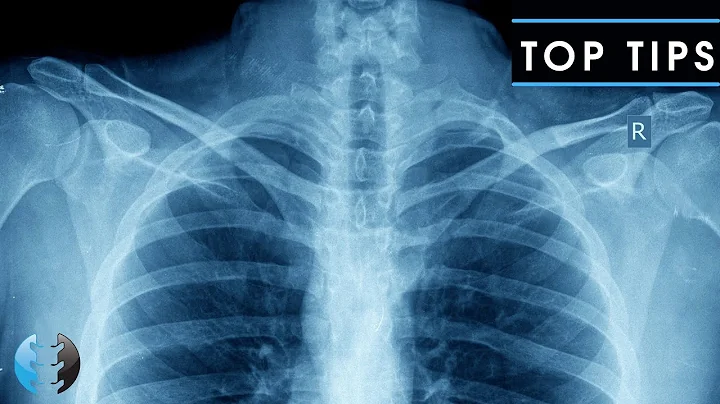

Reading A Chest X-ray